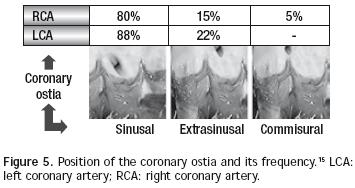

There are normally two coronary arteries: the right one (generally dominant, as it originates 70% of times the posterior descending artery) and the left one (which originates the anterior descending and circumflex arteries).14 Both arteries come from independent coronary ostia. According to the implantation height in relation with an imaginary line that joins the aortic sigmoid valves' junctions, coronary ostia location may be designed as sinusal, extra–sinusal or commissural. Habitually, the left coronary ostium is placed in a sinusal location in a higher percentage than the right ostium (88% vs 80%), as the latter is the only one that may be located commissuraly (5%). The extra–sinusal location is also more common in the left ostium (22%) than in the right one (15%) and commissural location of the left ostium is exceptional.15 Figure 5 illustrates these concepts and exposes frequency percentages of each of these types according to our studies.16 Coronary arteries layout may be very variable, but the most common pattern (68%) is originated from the left coronary trunk that starts at the level of the anterior valve and it is divided into anterior descendent and circumflex arteries, with the right coronary artery arising at the level of the left posterior valve. The second most common pattern (20%) is that of two independent coronary ostia, but with the circumflex artery arising from the right coronary artery. Other less common patterns are: single right coronary ostium (4.5%), inverted coronary arteries (3%), intramural coronary arteries (2%), and single left coronary ostium (1.5%).17 It is also worth stating that the main pathological variations of the coronary arteries are anomalous left coronary artery from the pulmonary artery (ALCAPA syndrome), and the coronary fistulae.